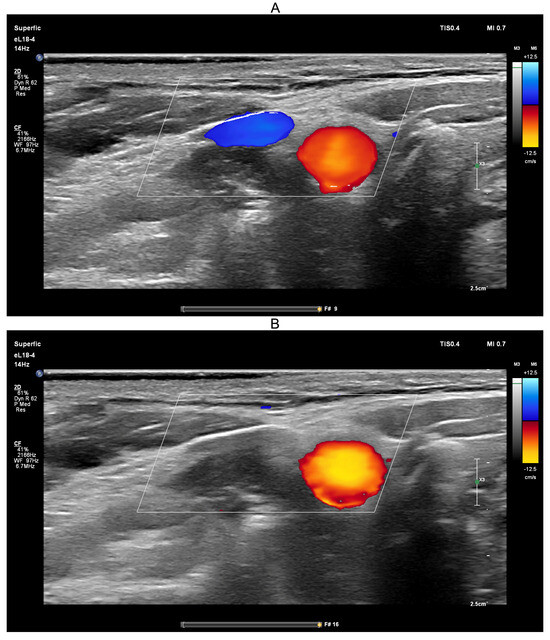

Ultrasound-guided compression of both jugular veins was performed on a healthy volunteer in the supine position for approximately 10 s using a PHILIPS EPIQ Elite ultrasound scanner (Figure 8).

Ultrasound guidance was used during the Queckenstedt test to confirm effective bilateral compression of the jugular veins. As shown in Figure 8A, color Doppler ultrasound demonstrated visible jugular venous flow (blue-coded) before compression, which disappeared during compression (Figure 8B), verifying successful occlusion. Simultaneously, carotid arterial flow (red-coded) remained unaffected, confirming selective venous obstruction.

Figure 8. Screenshots from the PHILIPS EPIQ Elite ultrasound triplex scanner during the ultrasound-guided jugular vein compression test (Queckenstedt’s test). (A)—Before compression of the jugular veins; (B)—During compression of the jugular veins.